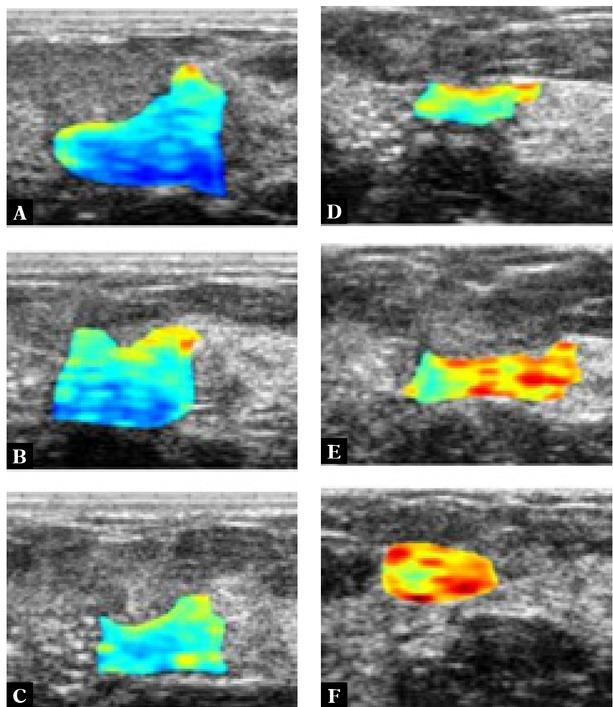

Fig. 1